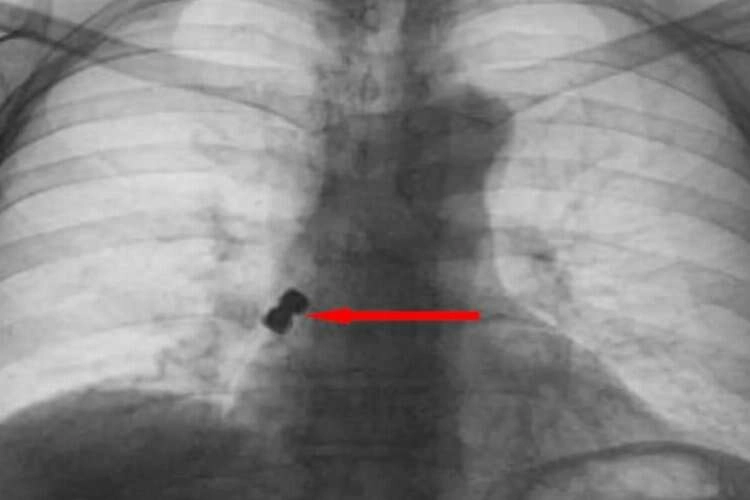

Yuttuğu dişler akciğerine kaçarak sağ nefes borusunu tıkayan 56 yaşındaki kadın ölümden döndü. Olay Emirdağ ilçesinde meydana geldi. İddiaya göre, Belçika’nın Brüksel kentinde yaşayan 56 yaşındaki D.K., isimli gurbetçi vatandaş implant diş tedavisi için Emirdağ’daki bir kliniğe gitti. Operasyon esnasında birbirine yapışık halde olan 2 adet implant bir anda hastanın dişinden düştü. İmplantlar ardından hasta yutkununca akciğerlere kaçıp sağ nefes borusunu tıkadı. Nefes almakta zorlanan D.K., ardından Emirdağ Devlet Hastanesi’ne kaldırıldı. Burada yapılan müdahalenin ardından D.K., Afyonkarahisar kent merkezindeki bir hastaneye sevk edildi. Burada D.K.’nın akciğerine kaçan implantlar cerrahi operasyona gerek kalmadan, bronkoskopi yöntemi adı verilen tıbbi müdahale ile çıkarıldı. İmplant yüzünden ölüm tehlikesi atlatan D.K., birkaç gün hastanede kaldıktan sonra taburcu edildi.